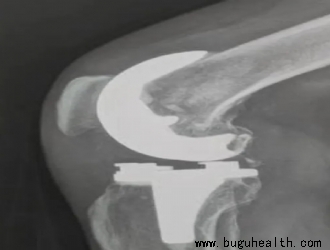

膝关节骨关节炎(KOA)是中老年人最常见的运动系统退行性疾病,其病理特征主要包括关节软骨变性破坏、软骨下骨硬化或囊性变、关节边缘骨质增生、滑膜病变、关节囊挛缩、韧带松弛或挛缩以及肌肉萎缩等根据病变部位不同可将膝关节骨关节炎分为单纯胫股关节骨关节炎(tibiofemoral osteoarthriti.....